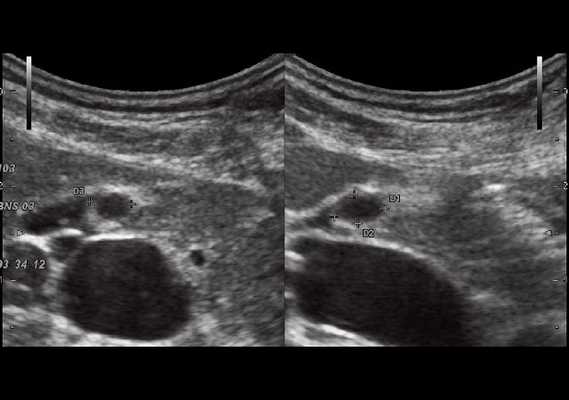

При УЗИ были выявлены диффузные изменения печени и поджелудочной железы, признаки хронического бескаменного холецистита, ангиомиолипома левой почки (без динамики за несколько лет), состояние после экстирпации матки с придатками. В левой подвздошной области соответственно зоне максимальной пальпаторной болезненности на протяжении 9 см отмечалось утолщение стенок толстой кишки до 6-7 мм (рис. 1). Перистальтика кишки отсутствовала, гаустрация была слабо выражена, при этом визуализировалось несколько болезненных при надавливании датчиком выпячиваний пониженной эхогенности, размером от 7 до 20 мм (рис. 2, а, б) с тонкой стенкой до 0,9-1,1 мм и наличием в некоторых из них фрагментов кишечного содержимого и газа (рис. 3, а, б).

Рис. 3. Эхографическая картина дивертикулита. Трансабдоминальное исследование конвексным датчиком 3,5 МГц.

При трансвагинальном УЗИ (рис. 4) также визуализировался фрагмент толстой кишки с утолщенными гипоэхогенными стенками и несколькими округлыми дивертикулами до 1 см в диаметре. Контуры одного из дивертикулов были неровными, он имел звездчатую форму. Отмечались утолщение и повышение эхогенности околокишечной жировой клетчатки по сравнению с контралатеральной стороной. При осмотре в режиме УЗ ангиографии утолщенная стенка кишки и дивертикулы были аваскулярными, окружающая клетчатка - гиперваскулярной.

Рис. 4. Эхографическая картина дивертикулита. Трансвагинальное исследование конвексным датчиком 7,5 МГц.

В приведенном наблюдении при УЗИ визуализировались множественные выпячивания истонченной кишечной стенки. На участках утолщенной стенки между дивертикулами и в самих дивертикулах сосудистый рисунок был обеднен или не визуализировался, что подтверждает роль сосудистого фактора в развитии болезни: сдавление внутристеночных сосудов с нарушением микроциркуляции, наличие ишемии и замедления венозного оттока. Некоторые дивертикулы были заполнены гомогенным аваскулярным содержимым средней эхогенности, без признаков внутрипросветного движения, так что содержимое сливалось с изображением стенки. В других дивертикулах пузырьки газа, выступая в качестве естественного контраста, позволили детально рассмотреть истонченную до 0,9-1,1 мм стенку кишки, лишенную гипоэхогенного мышечного слоя. Форма этих дивертикулов приближалась к шаровидной, устье было меньше, чем диаметр дивертикула. Однако встречались и выпячивания в форме конусов, с устьями, превышающими размеры самого дивертикула, в них прослеживалось продолжение гипоэхогенного мышечного слоя стенки.

Очевидно, эта разница в ультразвуковом изображении дивертикулов отражает стадии их формирования: округлые с истонченной стенкой и отсутствием в ней мышечного слоя - это сформированные дивертикулы, в то время как другие, в которых еще прослеживается мышечный слой или его фрагменты, - дивертикулы на стадии формирования.